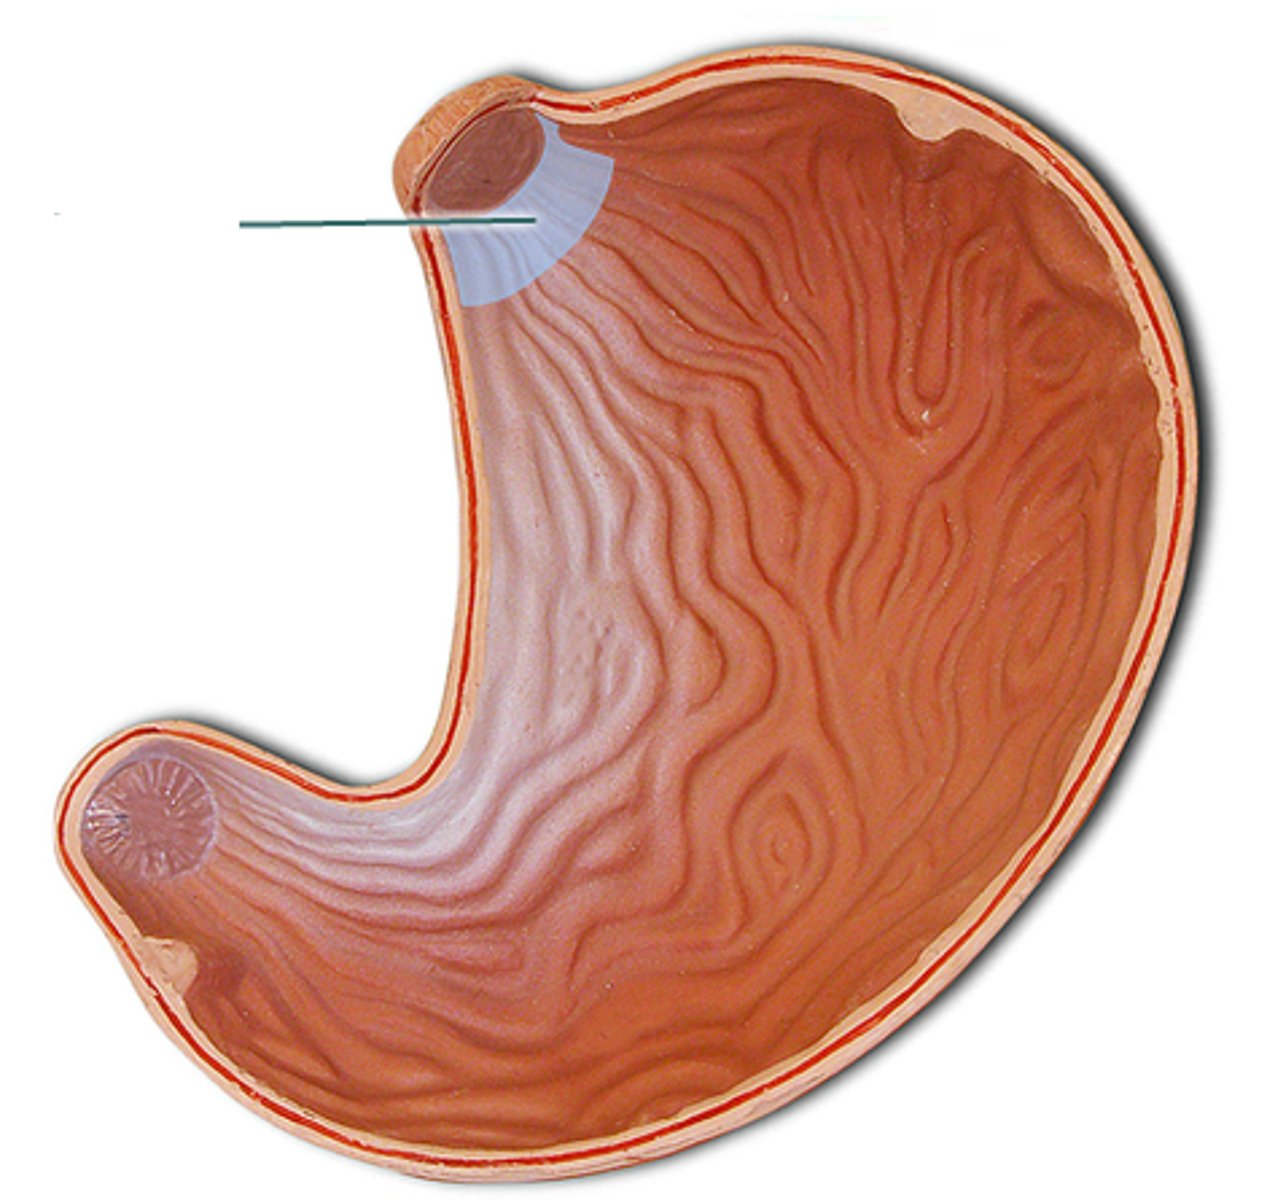

stomach

fundus

cardia

body

lesser curvature

greater curvature

cardiac sphincter / lower esophageal sphincter

pylorus

pyloric sphincter

rugae